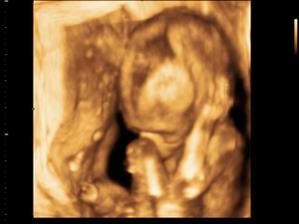

Baby # 3